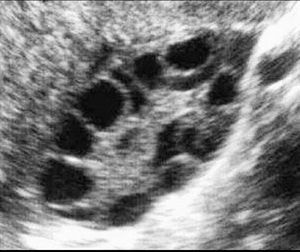

What is your diagnosis??

Polycystic ovary

PCOS

Pcod